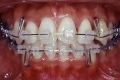

治療前後の比較